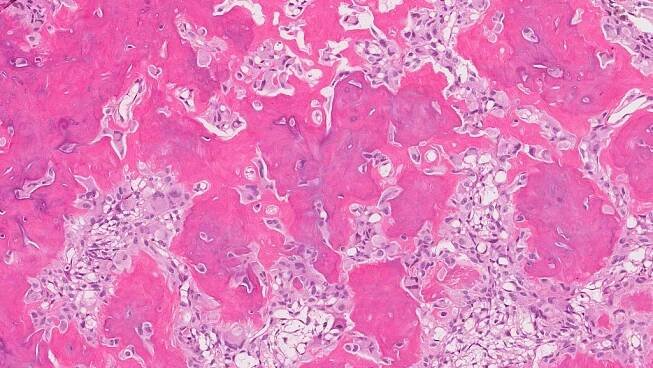

Tento obrázek ukazuje osteoidní osteom pozorovaný pod mikroskopem.

Osteoidní osteom je benigní nádor projevující se noční bolestivostí, která příznivě reaguje na acylpyrin. Vyskytuje se v koriové části kosti, kde edémem kolem sebe působí bolesti okostice.